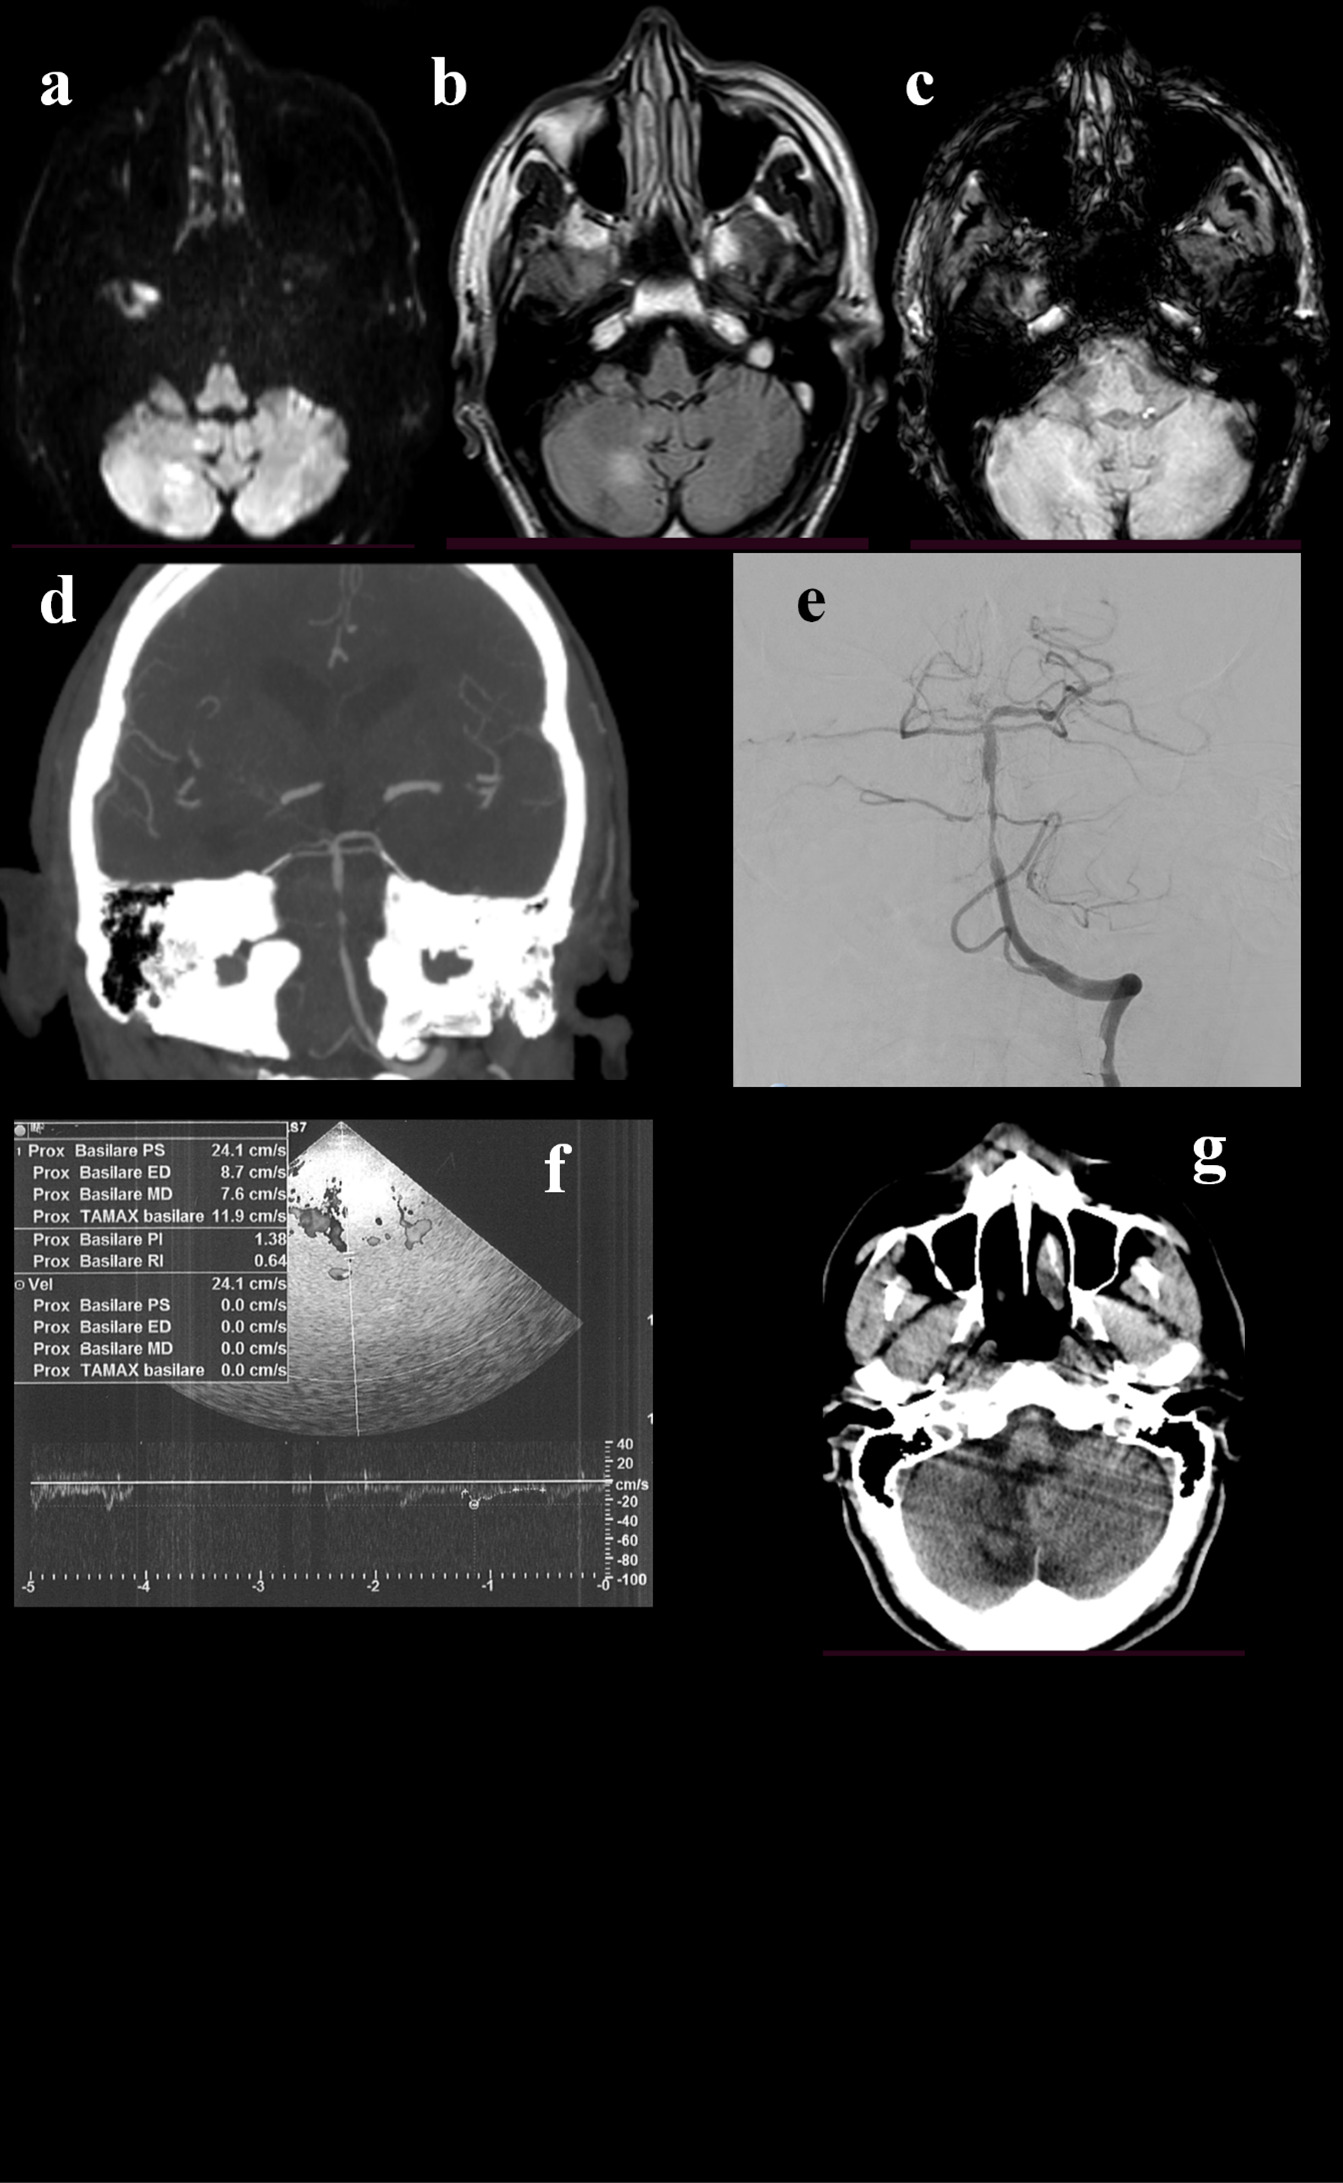

Figure 4. A 68-year-old man presented to the emergency department because of a 4-days-history of brief recurrent episodes of dizziness, nausea, vomiting, and sweating. He suffered from arterial hypertension, diabetes mellitus, and he had a spontaneous subarachnoid hemorrhage 4 years before. He was taking clopidogrel. During the episodes described before, the blood glucose was normal. The initial neurological examination did not show any abnormal findings. The brain CT scan and ORL examination were unremarkable. The brain MRI showed DWI-(a) and FLAIR-(b) positive lesion in the right cerebellar hemisphere, without hypointensities in SWI (c). CTA revealed stenosis at the middle portion of basilar artery (d), that was confirmed by DSA (e). TCCS was performed and pointed out basilar artery hemodynamics within normal range (f). In light of this, stenting was not performed. The 24-hours control head CT confirmed the right cerebellar region, without signs of further expansion of the ischaemic area or hemorrhage (g). The best medical treatment was adopted. The patient showed a progressive clinical improvement.